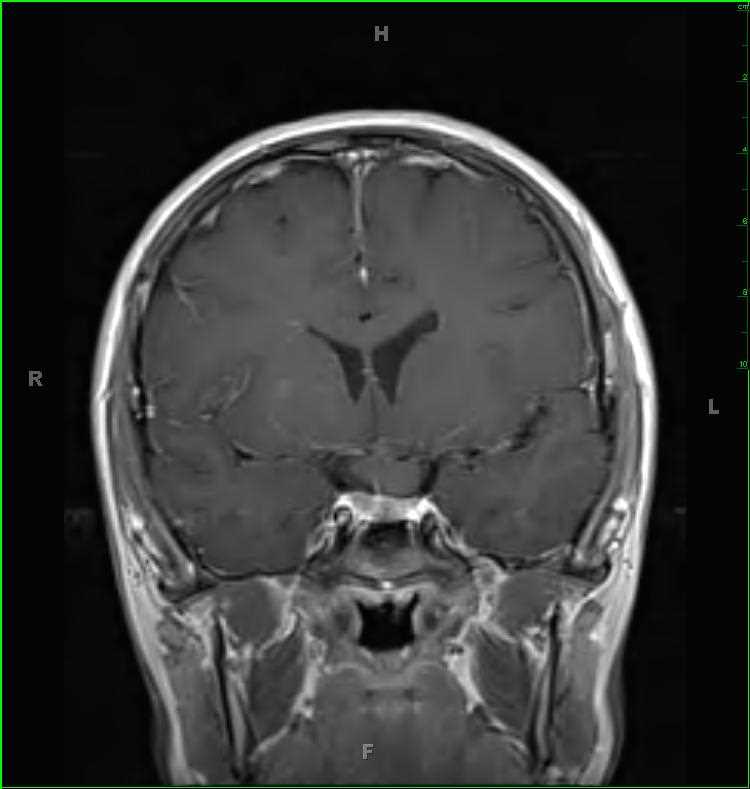

45-year-old female with chronic headaches. There is a well circumscribed, solid and cystic, T1-hypointense, T2/FLAIR-hyperintense, enhancing mass with increased blood volume centered on the foramen of Magendie. The mass enlarges the foramen spilling into both the cisterna magna and fourth ventricle. The differential includes ependymoma, subependymoma, choroid plexus papilloma, meningioma and metastatic disease, given the patients age. This was an anaplastic ependymoma. Ependymomas represent slow growing tumors of the ependymal cells. 2/3 are infratentorial with most centered in the fourth ventricle. Calcifications are common, and cysts and/or hemorrhage may be present. Despite the tumor having low cellularity, ADC values are typically low.